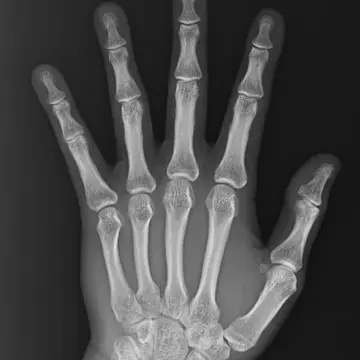

正常な第一関節

正常な第一関節。